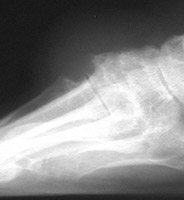

Gout: AP- Erosions 1st MTP joint with tophiGout: AP- Erosions 1st MTP joint with tophiTophaceus Gout: LateralTophaceus Gout: APGOUT is caused by monosodium urate or uric acid crystal deposition within cartilage, bone, or periarticular tissues.

Acute, episodic soft tissue swelling may represent the earliest radiographic sign. Later, sharp, round or oval marginal joint erosions with sclerotic borders are classically seen with gout. These findings most commonly occur along the dorsum of the foot. Associated soft tissue tophi or intraosseous nodules may be present. "Overhanging margin" occur where the bone resorbs beneath a tophaceous nodule. Joint spaces are usually preserved, but ankylosis may rarely occur with advanced stages of gout. The aforementioned findings may be in different stages of progression with any given patient.